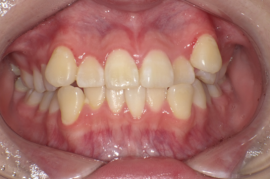

13歳8か月の女子(初診時:写真a)

主訴は左上に八重歯がある。右側Angle ClassII 左側Angle Class I、FMA 36.6°、A.L.D.(凸凹の量/上顎 -10.0mm、下顎 -4.0mm)

画像1: https://www.atpress.ne.jp/releases/360206/LL_img_360206_1.png

a:初診時